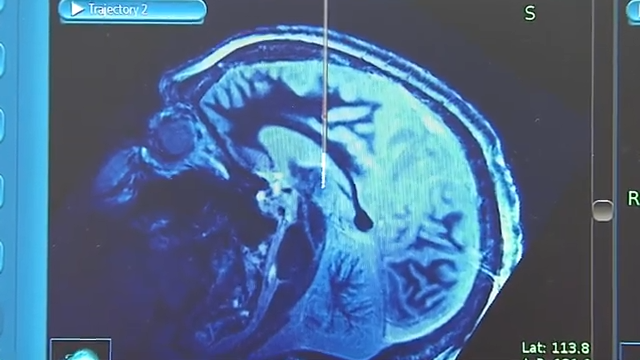

In the ER, doctors diagnosed her with a ruptured AVM in her frontal lobe.

Neurosurgeon at Washington University in St. Louis, Dr. Gregory Zipfel, explains, “It’s a tangle of blood vessels that you’re born with. Most people have it for many, many years, often for a few decades before they find out about it.”

Dr. Zipfel was able to remove part of Krysta’s skull. And using a high-powered microscope, he was able to seal off the AVM with special clips, and then remove it from surrounding brain tissue. Right after surgery, Krysta still suffered from the same symptoms.

DIAGNOSING: The symptoms of AVM differ depending on the size and placement of the cluster in the body. Some individuals don’t experience symptoms until their mid-30s. For women, pregnancy may expose symptoms for the first time or worsen them. This is due to the increased pressure on the blood vessels during that time. To properly diagnose an AVM, your doctor may order a CT scan or an MRI of the head, spine, and neck to closely assess your blood vessels. Your doctor might also use a stethoscope to listen for “bruit” – a loud rush of blood flow into your blood vessels sometimes caused by AVM.